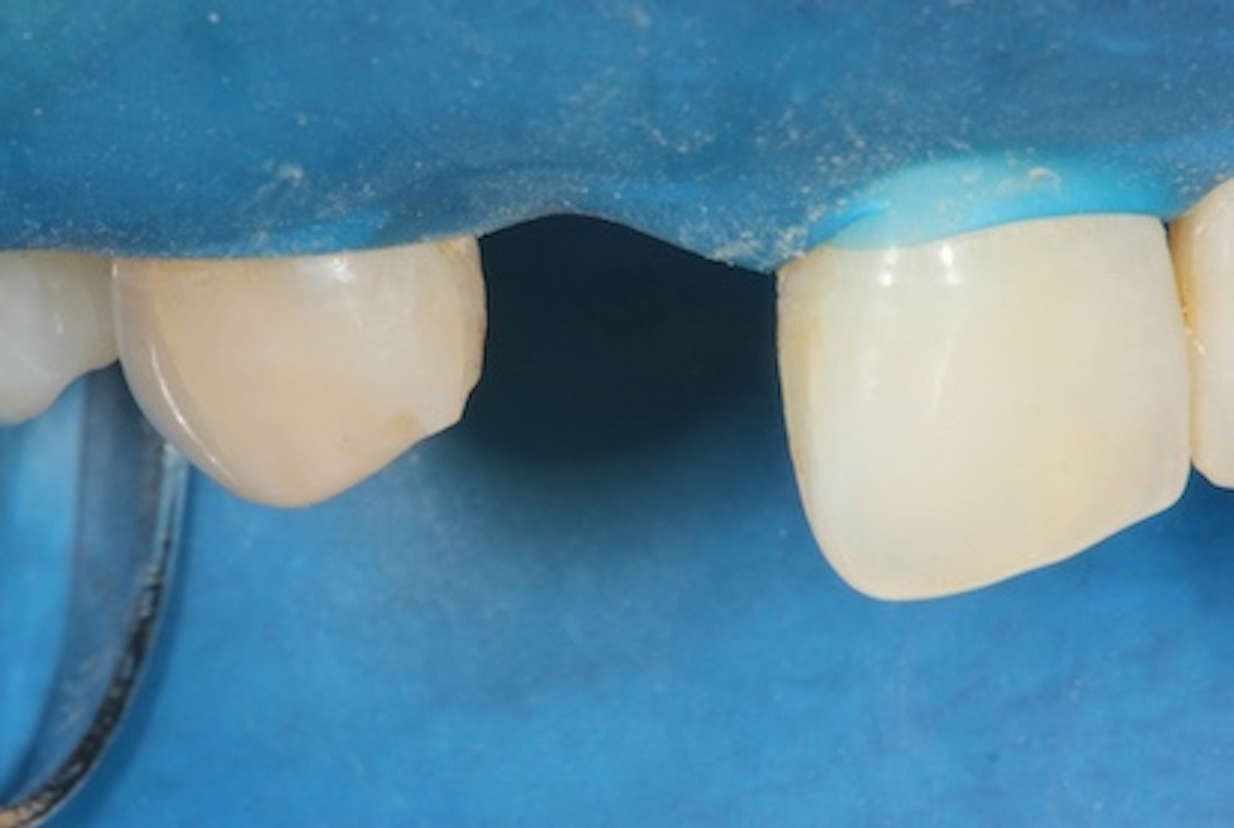

(3.) Placement of a rubber dam to achieve isolation.

Figure 3